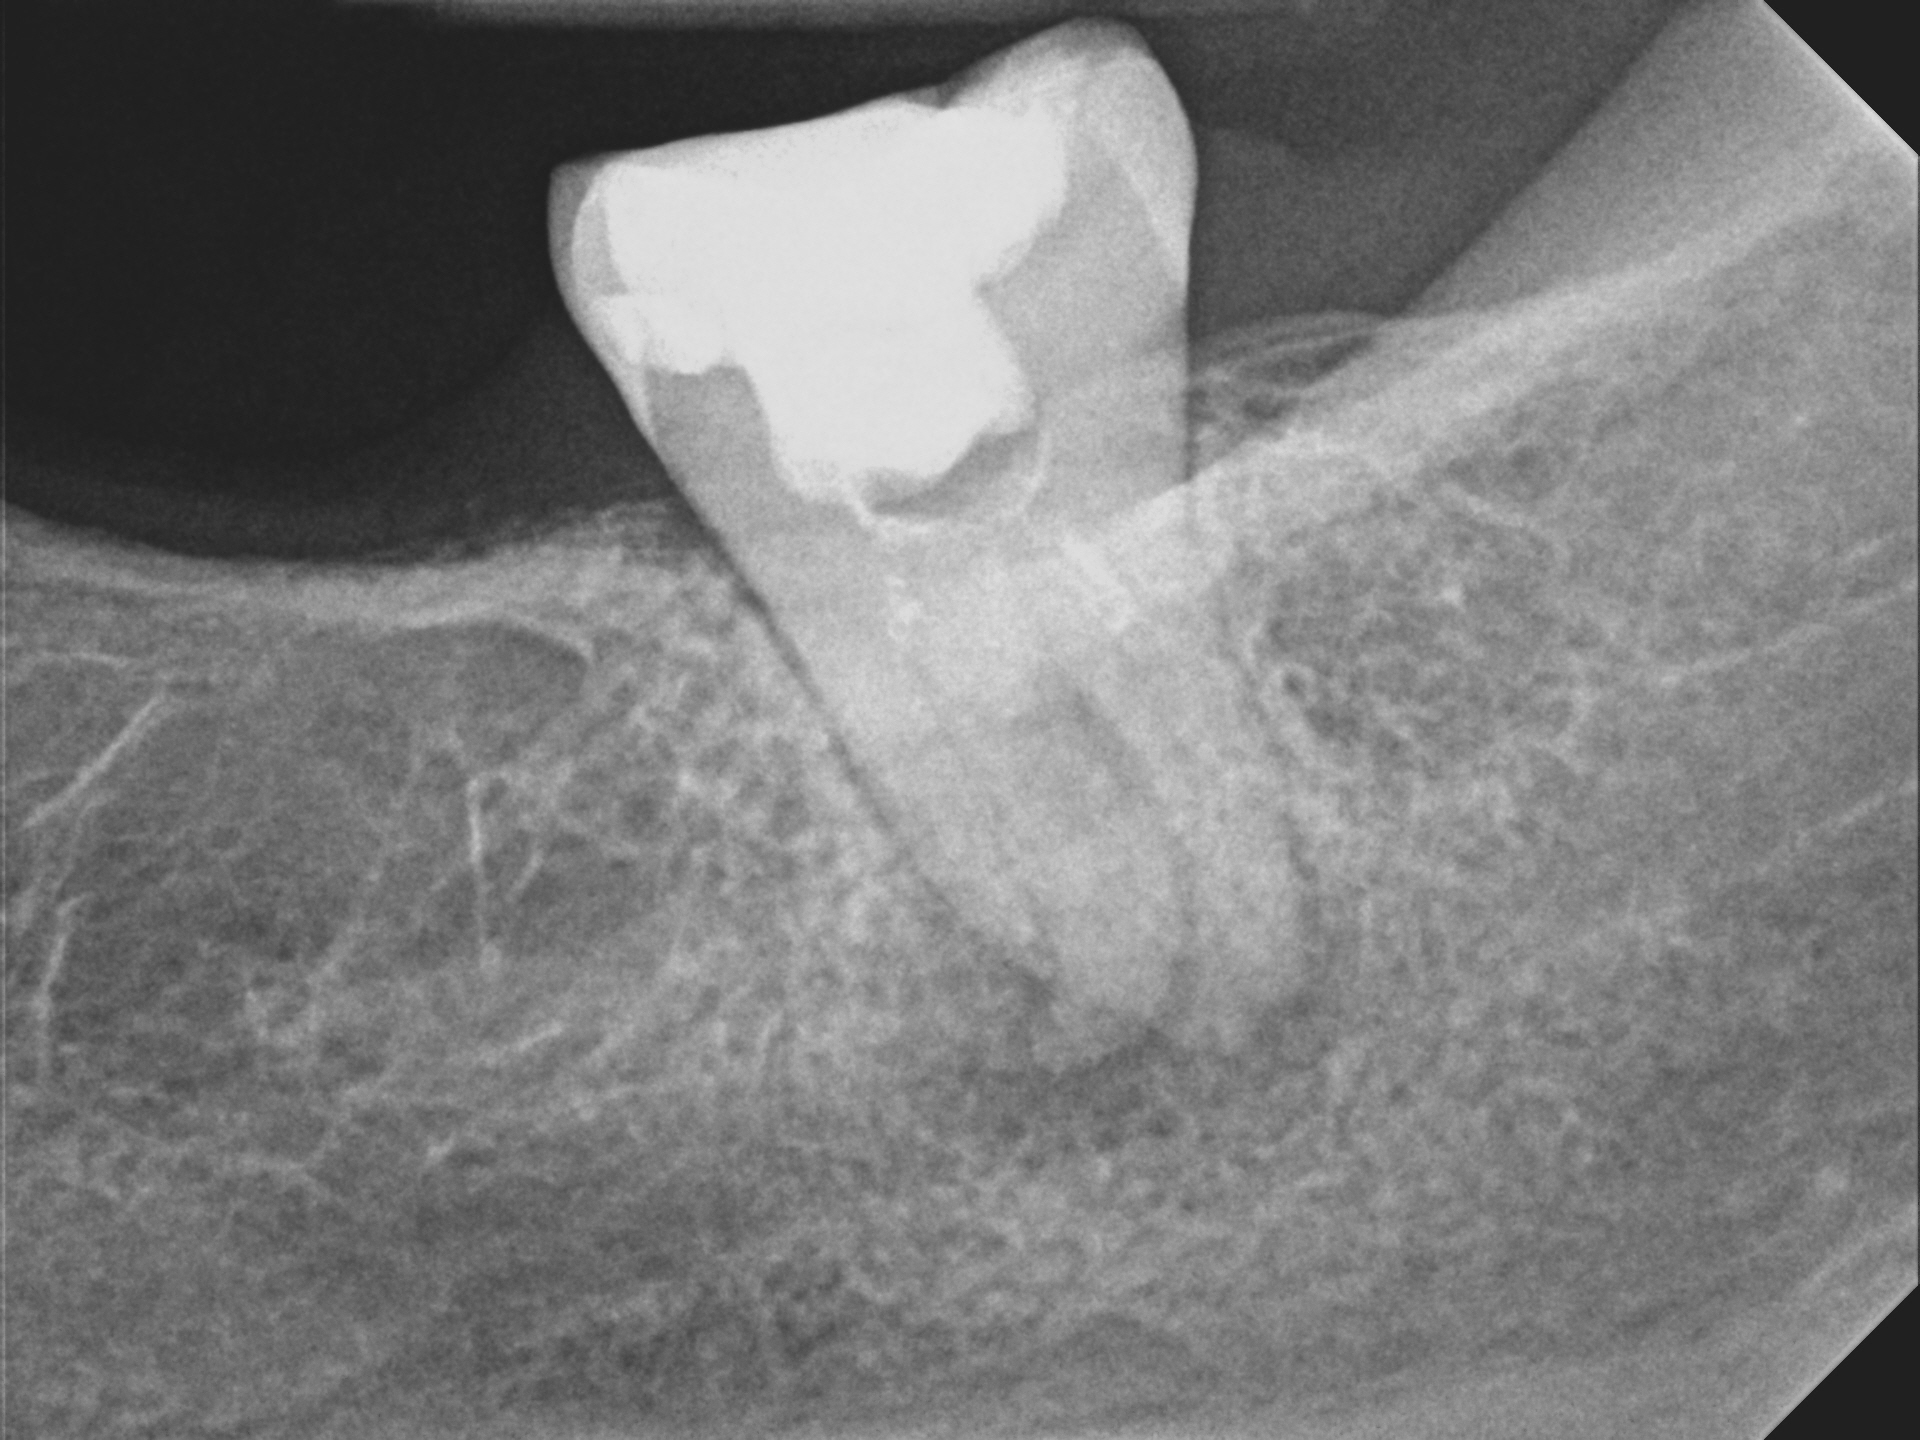

Case 3

The left images shows that the molar has one root shorter than the other--this is not how this tooth started out. This case shows that even the root of a tooth can be eroded away by a tooth infection, just like the bone, when an infection is present. The infection extended all around the back root--the dark areas around the tooth are infection-related bone loss. The front root had an infection just at the root tip. The right images shows complete healing.